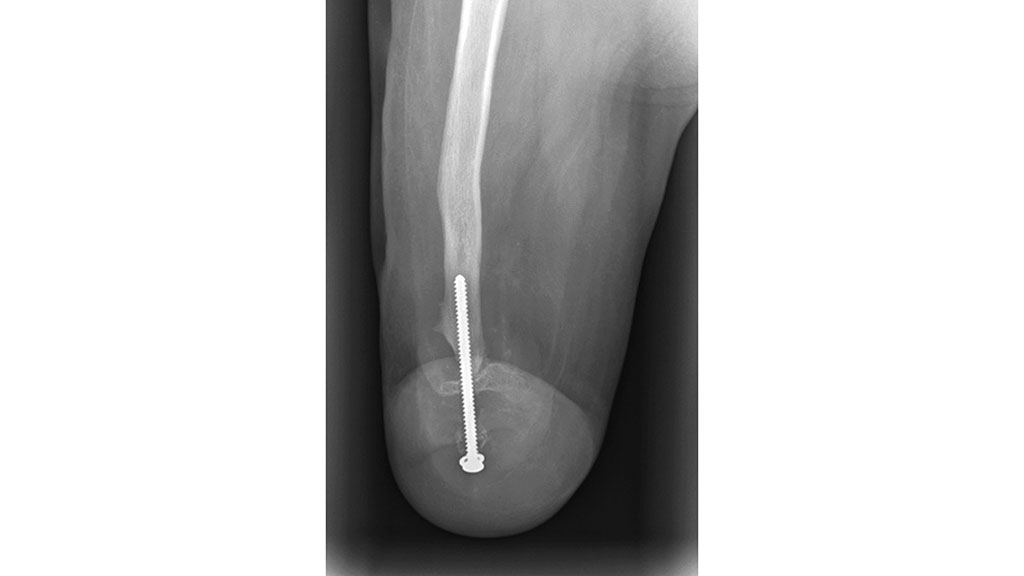

Mit fünf Jahren fusionierte man die einzelnen distalen Knochensegmente mit einer Schraube, die man nach einem halben Jahr entfernte (Abb. 13). Seither wird die Patientin mit längsovalen Schäften (M.A.S.) versorgt (Abb. 14). Die dafür verwendeten Fuß- und Kniepassteile brachte die Patientin in kürzester Zeit mit Defekten zurück, besonders die Vierachskniegelenke mit Federvorbringer. Bei der derzeitigen Versorgung nutzten die Orthopädie-Techniker ein einachsiges Kniegelenk mit Hydraulik und den Pediatric-Prothesenfuß (Abb. 15).